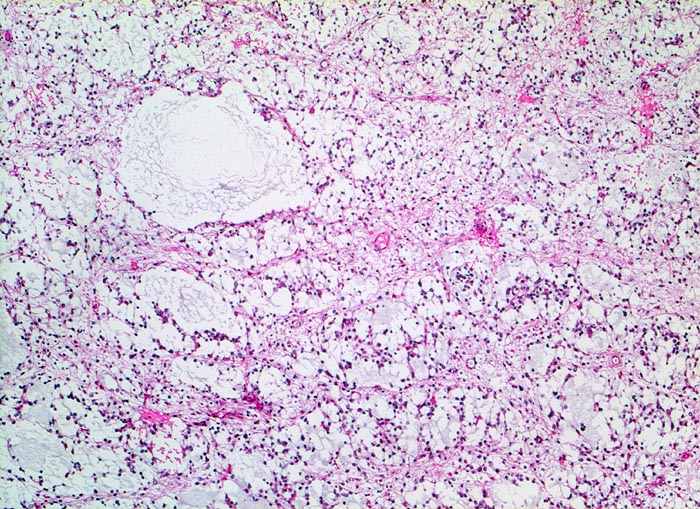

Histologisch bestehen die Oligodendrogliome aus kompakten Aggregaten runder Zellen mit deutlichen Zellgrenzen und klarem Zytoplasmasaum um einen dichten runden zentralen Kern (“Spiegelei”). Die Vakuolisierung des Zytoplasma stellt einen Fixationsartefakt dar und fällt bei Schnellschnitten als diagnostisches Hilfsmittel weg (Gefrierschnitt!). Charakteristisch sind verzweigte Kapillaren. Die Tumorzellen infiltrieren die Hirnrinde diffus und können sich bis in die Meningen ausbreiten.

• Fokale mukoide/zystische Degeneration innerhalb des Tumors mit Ausbildung von Pseudozysten.

• Dichtes Netzwerk verzweigender Kapillaren.

• Tumorzellen umgeben von einem Halo ("Spiegeleier").